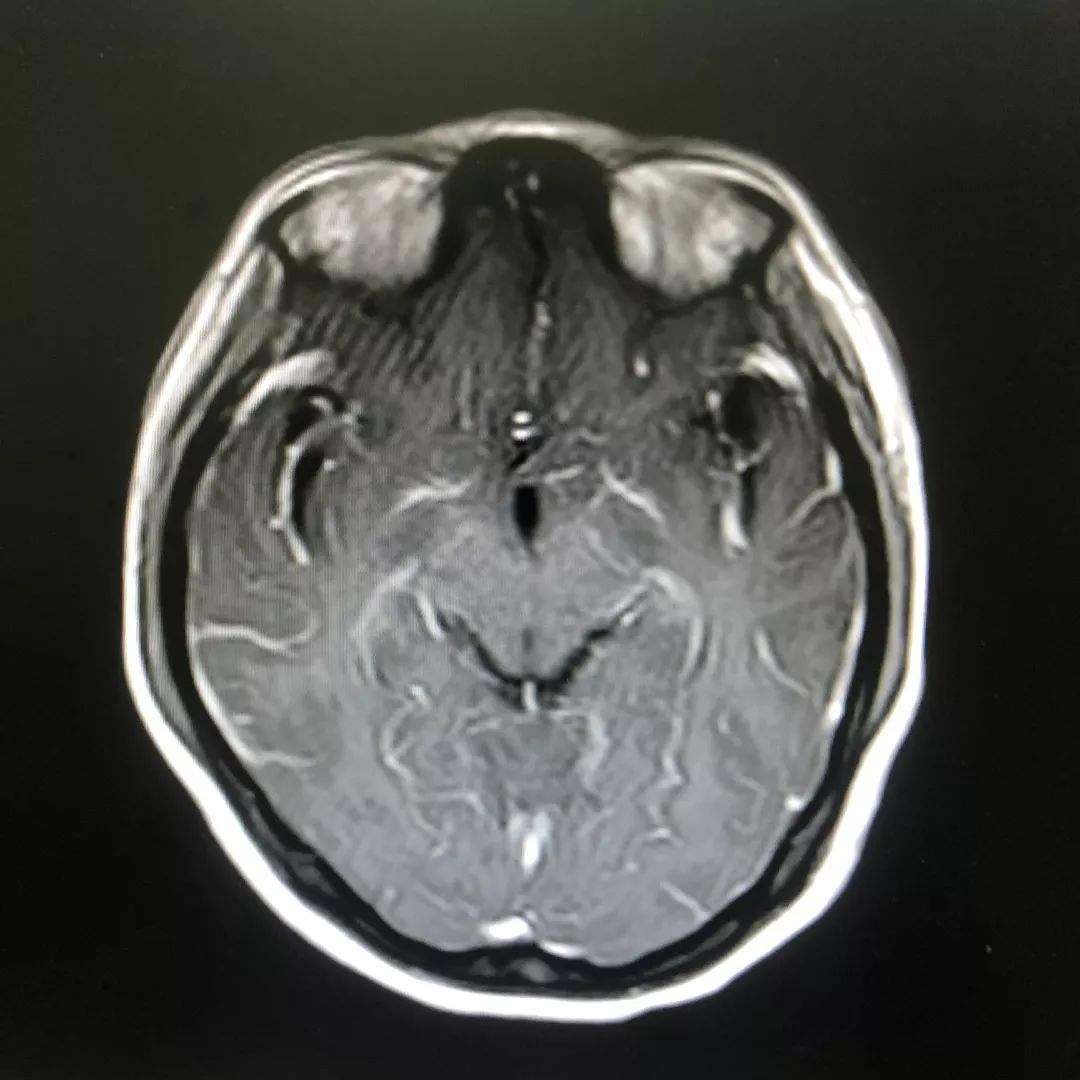

头颅增强磁共振:脑膜多发线样增强影

根据林女士发热、头痛,且出现精神行为异常、局部神经功能受损,查体可见明显的脖子僵硬,转颈和低头困难等症状,以及腰椎穿刺术及头颅磁共振增强检查等检查结果,医院神经内科专家高度怀疑结核性脑膜炎(一类难确诊、高病死率的疾病)可能,并立即启动了抗结核治疗。